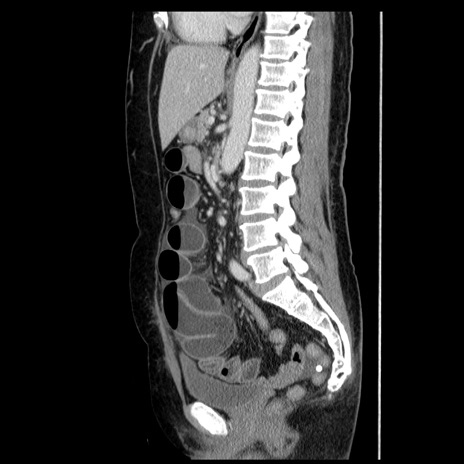

症例6(矢状断像)

【症例】50歳代女性

【主訴】下腹部痛

【現病歴】本日朝より下痢2回あり。 昼食を食べた後、嘔吐3回、下腹部痛認め、症状軽快せず、当院救急搬送。

最終食事:本日昼(生ものなし)。 昨日の夜、刺身を食ぺたとのこと。周囲に同様の症状の者なし。普段、排便は毎日あるとのこと。

【既往歴】卵巣癌術後(8年前に当院で卵巣摘出)

【身体所見】 意識清明、腹部:平坦、腸蠕動音→、やや硬、下腹部自発痛・圧痛あり、反跳痛あり、筋性防御なし。

【データ】WBC 16000、CRP 0.01